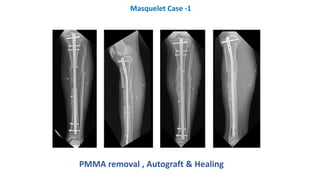

Masquelet Case -1 (Autograft)

PMMA removal , Autograft & Healing

Masquelet Case -1